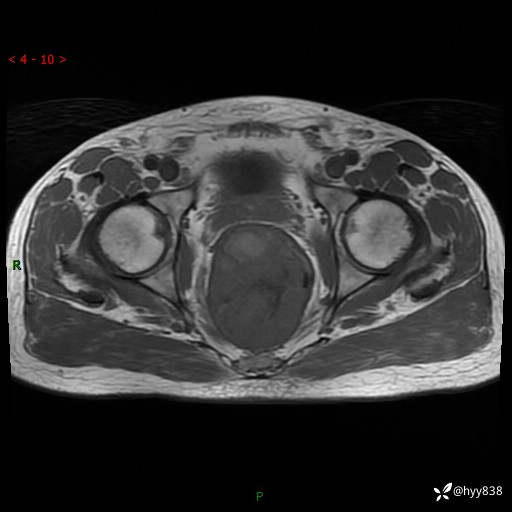

盆腔MRI平扫